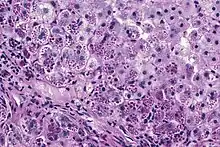

With A1AT deficiency, the pathogenesis of the lung disease is different from that of the liver disease, which is caused by the accumulation of abnormal A1AT proteins in the liver, resulting in liver damage.[9] As such, lung disease and liver disease of A1AT deficiency appear unrelated, and the presence of one does not appear to predict the presence of the other.[9] Between 10 and 15% of people with the PiZZ genotype will develop liver fibrosis or liver cirrhosis, because the A1AT is not secreted properly and therefore accumulates in the liver.[18] The mutant Z form of A1AT protein undergoes inefficient protein folding (a physical process where a protein chain achieves its final conformation). 85 percent of the mutant Z form are unable to be secreted and remain in the hepatocyte.[9] Nearly all liver disease caused by A1AT is due to the PiZZ genotype, although other genotypes involving different combinations of mutated alleles (compound heterozygotes) may also result in liver disease.[9] A liver biopsy in such cases will reveal PAS-positive, diastase-resistant inclusions within hepatocytes.[9] Unlike glycogen and other mucins which are diastase sensitive (i.e., diastase treatment disables PAS staining), A1AT deficient hepatocytes will stain with PAS even after diastase treatment - a state thus referred to as "diastase resistant". The accumulation of these inclusions or globules is the main cause of liver injury in A1AT deficiency. However, not all individuals with PiZZ genotype develop liver disease (incomplete penetrance), despite the presence of accumulated mutated protein in the liver.[9] Therefore, additional factors (environmental, genetic, etc.) likely influence whether liver disease develops.[9]